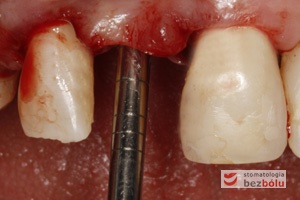

Ustalenie pozycji implantu - wiertło Lindemana wyznacza nachylenie i oś długą dla wprowadzanego implantu

Ustalenie pozycji implantu – wiertło Lindemana wyznacza nachylenie i oś długą dla wprowadzanego implantu